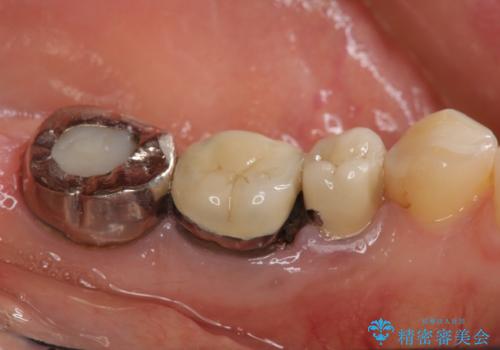

X線写真・視診より歯の破折クラウン下の虫歯再発が認められます。

クラウンの除去・虫歯の除去、根管治療を行ったのち、上顎は強い咬合力に対し破折抵抗性のある咬合面をメタルにしたメタルボンドによる補綴を計画します。